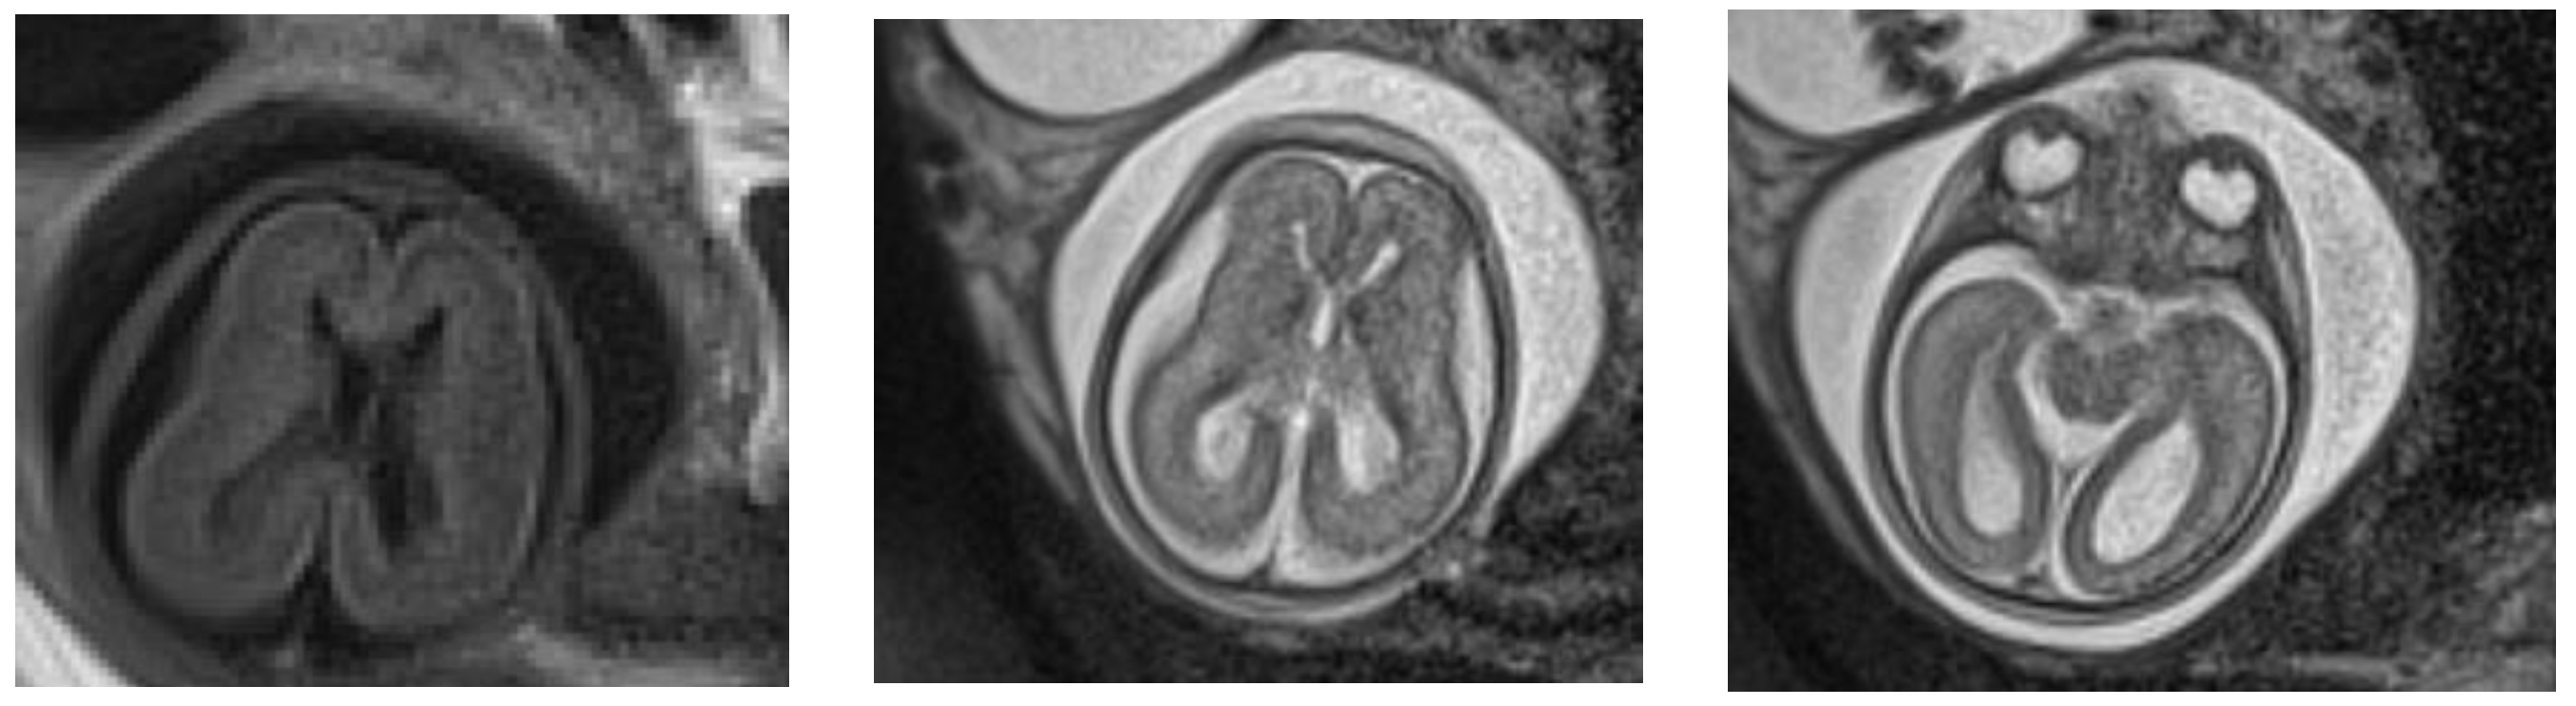

Figure 1.

MRI at 24 weeks of gestation: no Sylvian fissure are seen; ventricular dilatation; the parieto-occipital and Sylvian fissures appear flat and the subarachnoid space is increased.